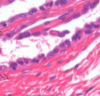

הסלייד הבא נלקח ממערכת הרביה הזכרית, מה רואים בו?

מה מסומן בחץ מספר 2?

Seminiferous tubules

Spermatid

הסלייד הבא נלקח ממערכת הרביה הזכרית, מה רואים בו?

מה מסומן בחץ מספר 1?

Seminiferous tubules

Spermatogonium

הסלייד הבא נלקח ממערכת הרביה הזכרית, מה רואים בו?

מה מסומן בחץ מספר 3?

Seminiferous tubules

Primary Spermatocyte